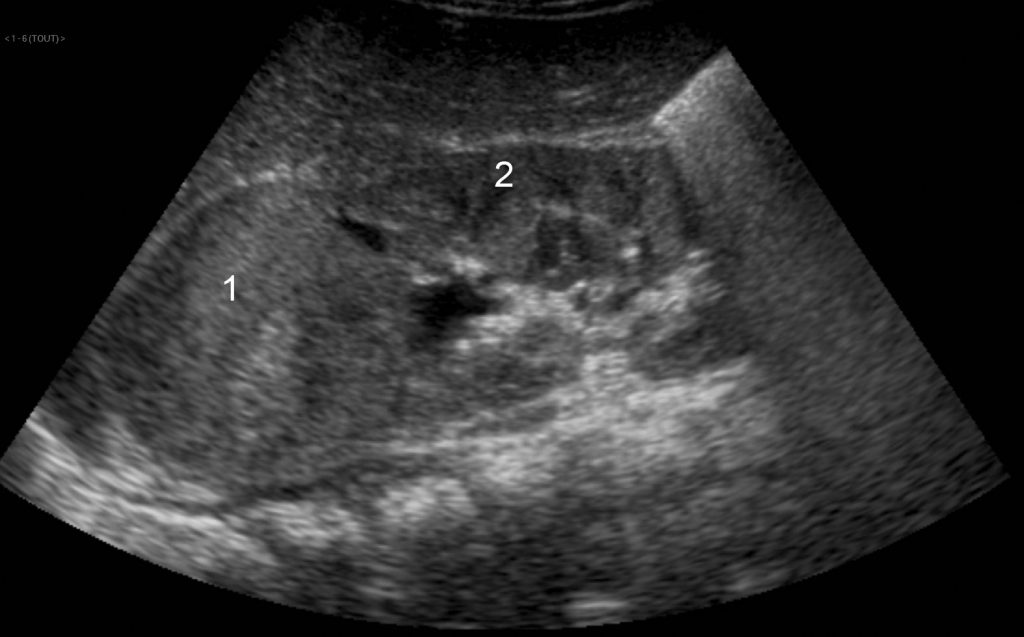

Devant une masse abdominale, l’échographie est l’examen de première intention. Elle permet de déterminer l’organe dont dépend la tumeur et participe au bilan d’extension de la lésion (figures 105.1 et 105.2).

Fig. 105.1 Coupe longitudinale sur le flanc droit chez un enfant de 2 ans.

L’échographie met en évidence une masse (1) développée aux dépens du pôle supérieur du rein (2). Cette masse est d’échostructure tissulaire. L’âge de l’enfant, la localisation rénale et le caractère tissulaire suggèrent fortement le diagnostic de néphroblastome.

Source : CERF, CNEBMN, 2022.